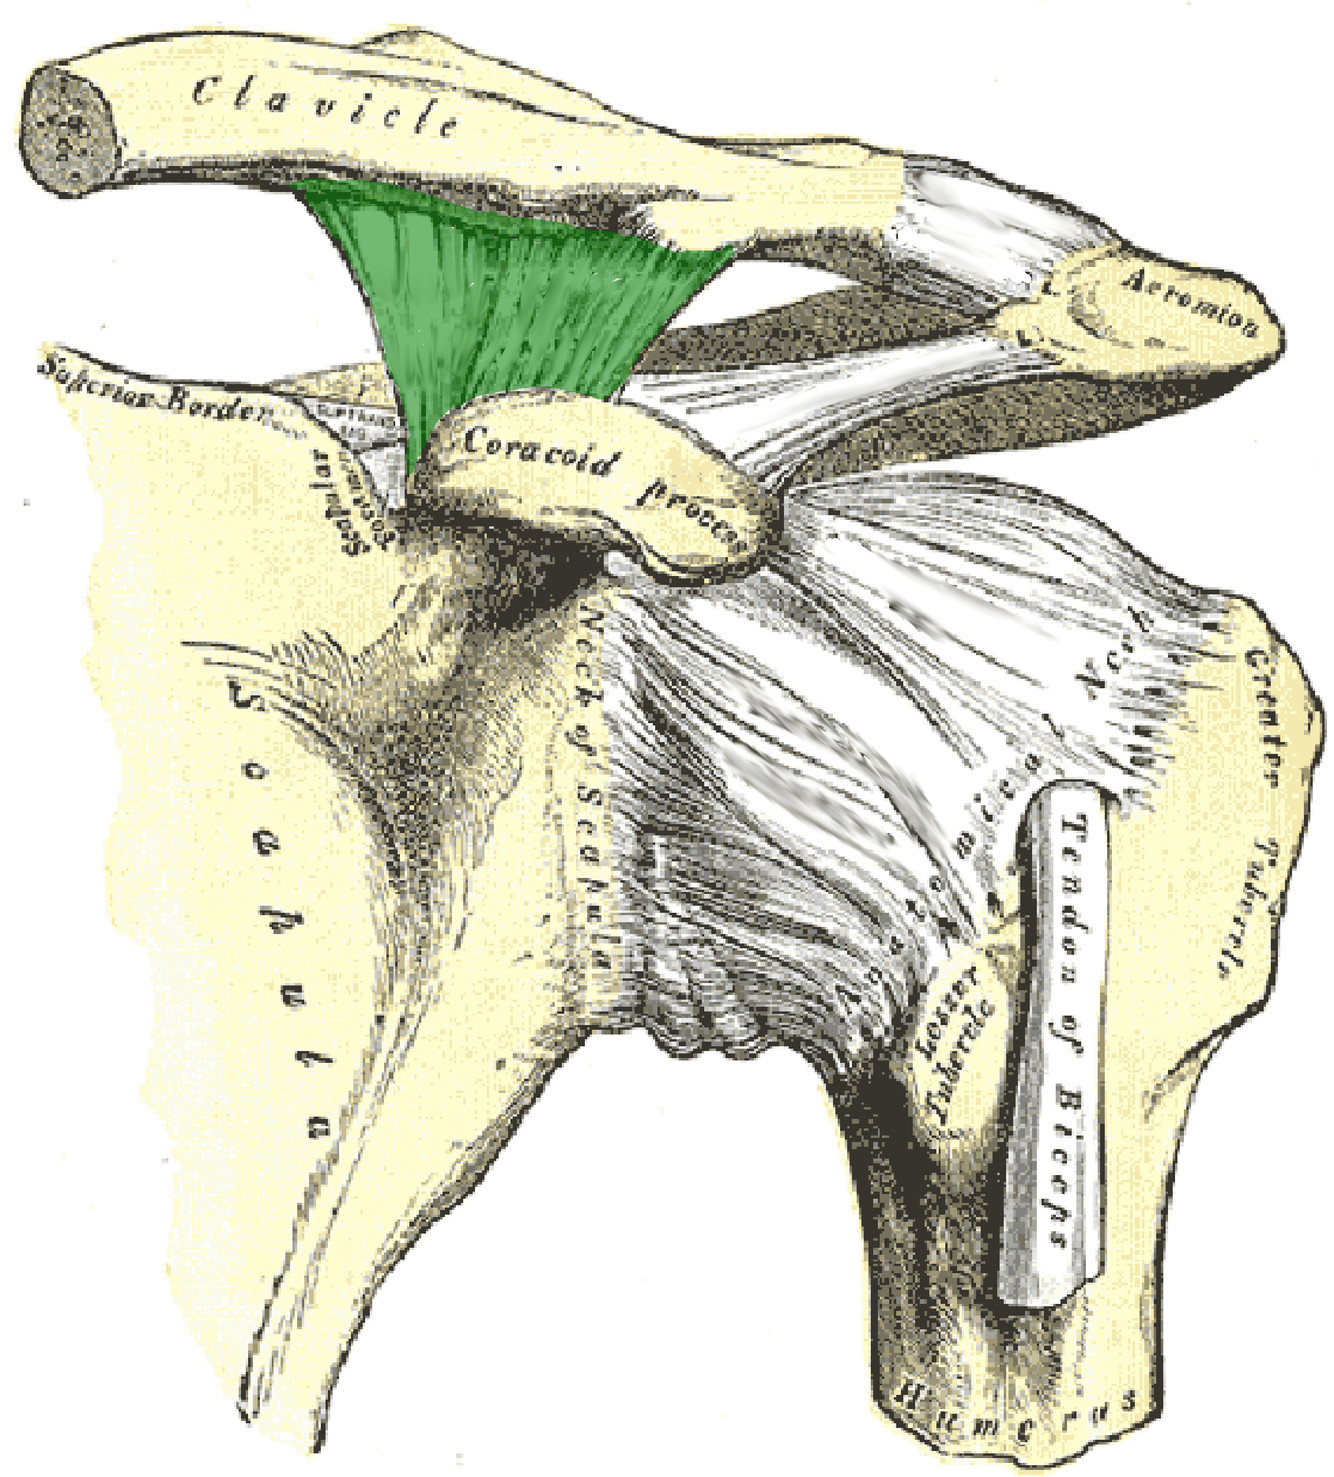

What is this structure?

Coracoclavicular ligament of the shoulder